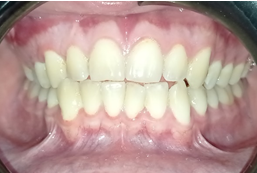

En el examen bucal se observó una apertura bucal normal (50 mm), mucosa oral húmeda y sin lesiones, lengua central y móvil, unidades dentarias presentes, fórmula dentaria permanente, sin caries ni restauraciones. En el cuadrante superior derecho se notó un aumento de volumen del contorno vestibular desde la unidad dental 1.3 hasta la unidad 1.7; no fue posible palpar el límite superior de la lesión. En la mucosa involucrada se observó un cambio en la coloración de la encía adherida, debido a la isquemia provocada por el aumento de volumen óseo tal como se muestra en la Figura 2.

Figura 2. Fotografía donde se observa aumento y deformidad del contorno vestibular en la hemiarcada superior derecha.

Fuente: Historia Clínica Postgrado Cirugía bucal ULAC-IDOLA Julio 2021.